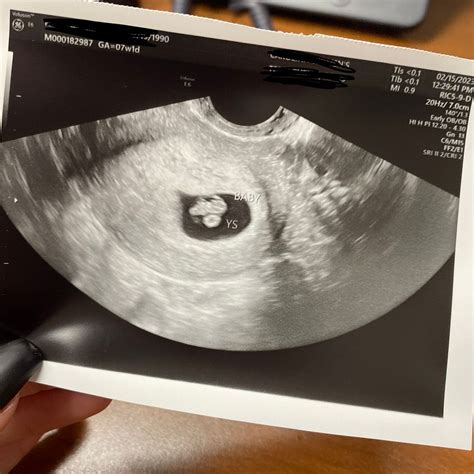

During a 7 week pregnancy sonography, the ultrasound technician will look for several key indicators of fetal development. These include:

• The presence of a gestational sac, which is the earliest sign of pregnancy visible on ultrasound.

• The yolk sac, which provides early nutrition to the embryo.

• The embryo itself, which should be visible as a small, curved structure within the gestational sac.

• The fetal pole, which is the earliest visible part of the embryo.

• The heartbeat, which may be detectable by this week, although it is not always visible at 7 weeks.

If the heartbeat is not detected, it is not necessarily a cause for concern, as it can sometimes be too early to see. The technician will also measure the size of the gestational sac and the crown-rump length (CRL) of the embryo, which helps to estimate the gestational age and ensure that the pregnancy is progressing normally.

At 7 weeks, the embryo is still very small, measuring about 10,000 times smaller than a newborn baby. However, significant development is occurring. Some of the common findings during a 7 week pregnancy sonography include:

• The embryo is curved, with a distinct head and tail.

• The neural tube, which will eventually form the brain and spinal cord, is beginning to close.

• The heart is developing rapidly, and the heartbeat may be visible.

• The placenta is starting to form, providing essential nutrients and oxygen to the embryo.